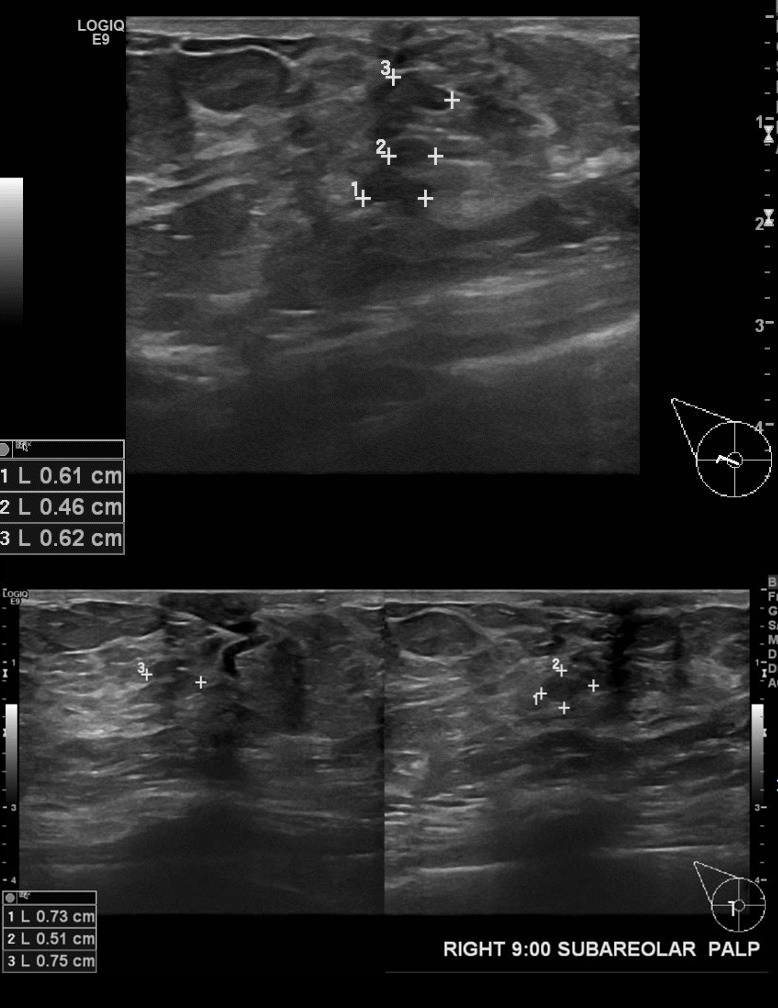

상기환자 우측유두분비물로 2014년부터 추적관찰하시던 60대여자분으로

2016년 6월  초음파 진행하고 우측유방 7시~9시방향으로 Excision 시행한후

침윤성유관암 진단되셨습니다